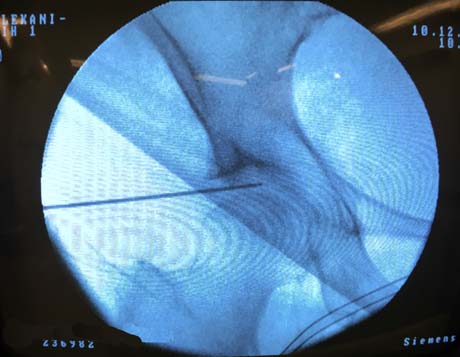

The special needle is inside in arthritic hip joint under fluoroscopic vision

Fluoroscopic vision, the needle is inside the hip joint